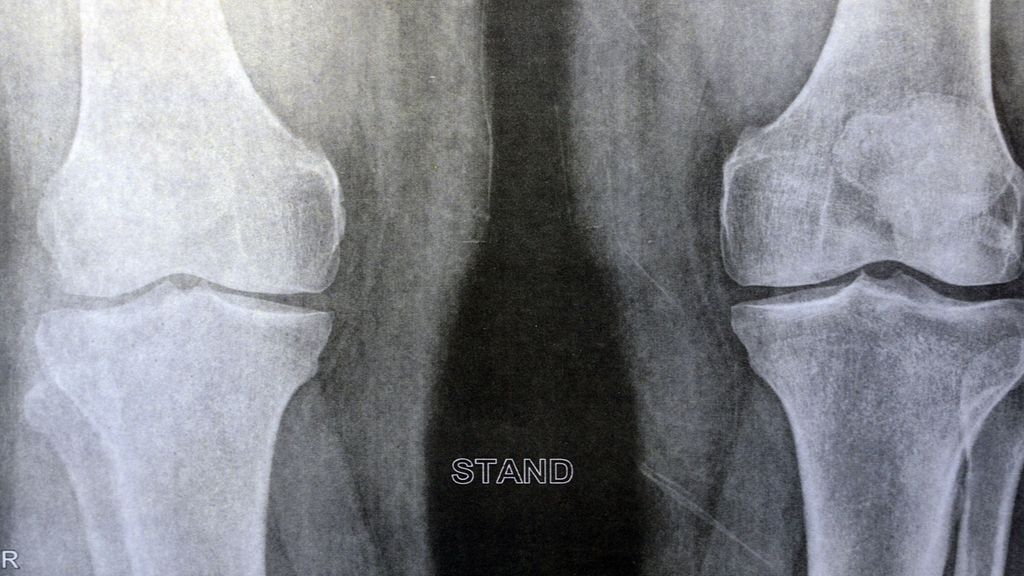

Die Kalzifikation bei Arthrose lasse sich in Röntgenbildern erkennen und quantifizieren, erklärte Prof. Dr. rer. nat. Jessica Bertrand, Magdeburg, bei ihrem Vortrag am DGRh-Kongress 2024. Dies habe ihre Arbeitsgruppe genutzt, um die Verkalkung im Gelenkspalt in Graden zu beschreiben. Bei Grad 1 lägen winzig kleine Verkalkungen vor, bei Grad 2 etwas mehr und bei Grad 3 eine Chondrokalzinose. Allerdings korrelierten diese Verkalkungsgrade wenig mit dem Kellgren-Lawrence-Score, also dem radiologischen Schweregrad der Arthrose: Es gebe sowohl Menschen mit schwerer Arthrose, die radiologisch keine Verkalkung zeigten, als auch solche mit einer leichter Arthrose und radiologisch schwerer Verkalkung. Für die radiologisch nachgewiesene Gelenkverkalkung seien basische Kalziumphosphatkristalle (BCP) sowie Kalziumpyrophosphatkristalle (CPP) verantwortlich.